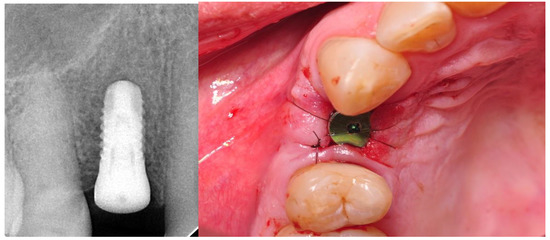

- Implantation: intraoperative and postoperative RVG (radiovisiography—Planmeca OY, Helsinki, Finland), gingival biotype assessment thick/thin;

- Four weeks after the implantation: intraoral scan, screw-retained prosthetic, RVG;

2.4. Surgical Phase

2.5. Prosthetic Phase